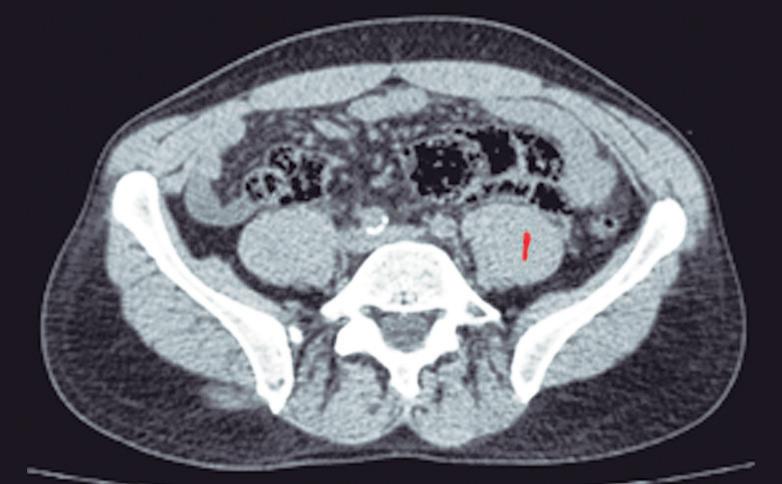

Se refiere a la presencia de tejido pancreático fuera de su ubicación normal y sin conexión con el parénquima glandular principal. Su localización más frecuente es en el tracto gastrointestinal, con mayor prevalencia en el estómago y duodeno, aunque también puede estar presente en otros sitios como el mesenterio, epiplones e incluso en el hígado (Figuras 11 y 12). La hipótesis más aceptada es que corresponde a la proliferación de tejido pancreático a partir de restos celulares de los brotes embriológicos.

A) Tomografía computada con contraste, plano axial. Presencia de tejido ectópico pancreático en topografía del epiplón menor. B) Tomografía computada con contraste, plano axial, corte más caudal. Sector de reemplazo graso difuso en el interior de la heterotopía pancreática (flecha). C) Tomografía computada con contraste, plano coronal. Las flechas señalan el páncreas ectópico en topografía del epiplón menor, en contacto con el estómago (cabeza de flecha).

Figura 11. Páncreas ectópico

A) Tomografía computada con contraste, plano axial. Flechas: Páncreas anular. Cabeza de flecha: Páncreas ectópico en la 1° porción del duodeno. B) Tomografía computada con contraste, plano coronal. Flecha: Páncreas anular. Cabeza de flecha: Páncreas ectópico en la 1° porción del duodeno.

Si bien suele ser asintomática la heterotopía pancreática está formada por tejido funcionante que por lo tanto es susceptible a sufrir las mismas patologías que el páncreas normotópico, pudiendo desarrollar pancreatitis e incluso dar lugar a tumores exocrinos (adenocarcinoma) y endocrinos.20

El diagnóstico diferencial del páncreas ectópico es con las lesiones extramucosas gástricas y duodenales, en particular el tumor del estroma gastrointestinal. En los estudios imagenológicos la heterotopía muestra un aspecto “glandular” similar al del páncreas. Por otra parte, exhibe refuerzo similar al páncreas en las secuencias diná-

micas post-contraste obtenidas en las fases arterial-parenquimatosa pancreática y portal. La colangio-RM, debido a su mayor resolución tisular, ofrece ventajas frente a la TC, mostrando el tejido ectópico con similar intensidad de señal (en todas las secuencias de pulso) a la glándula pancreática.23,24